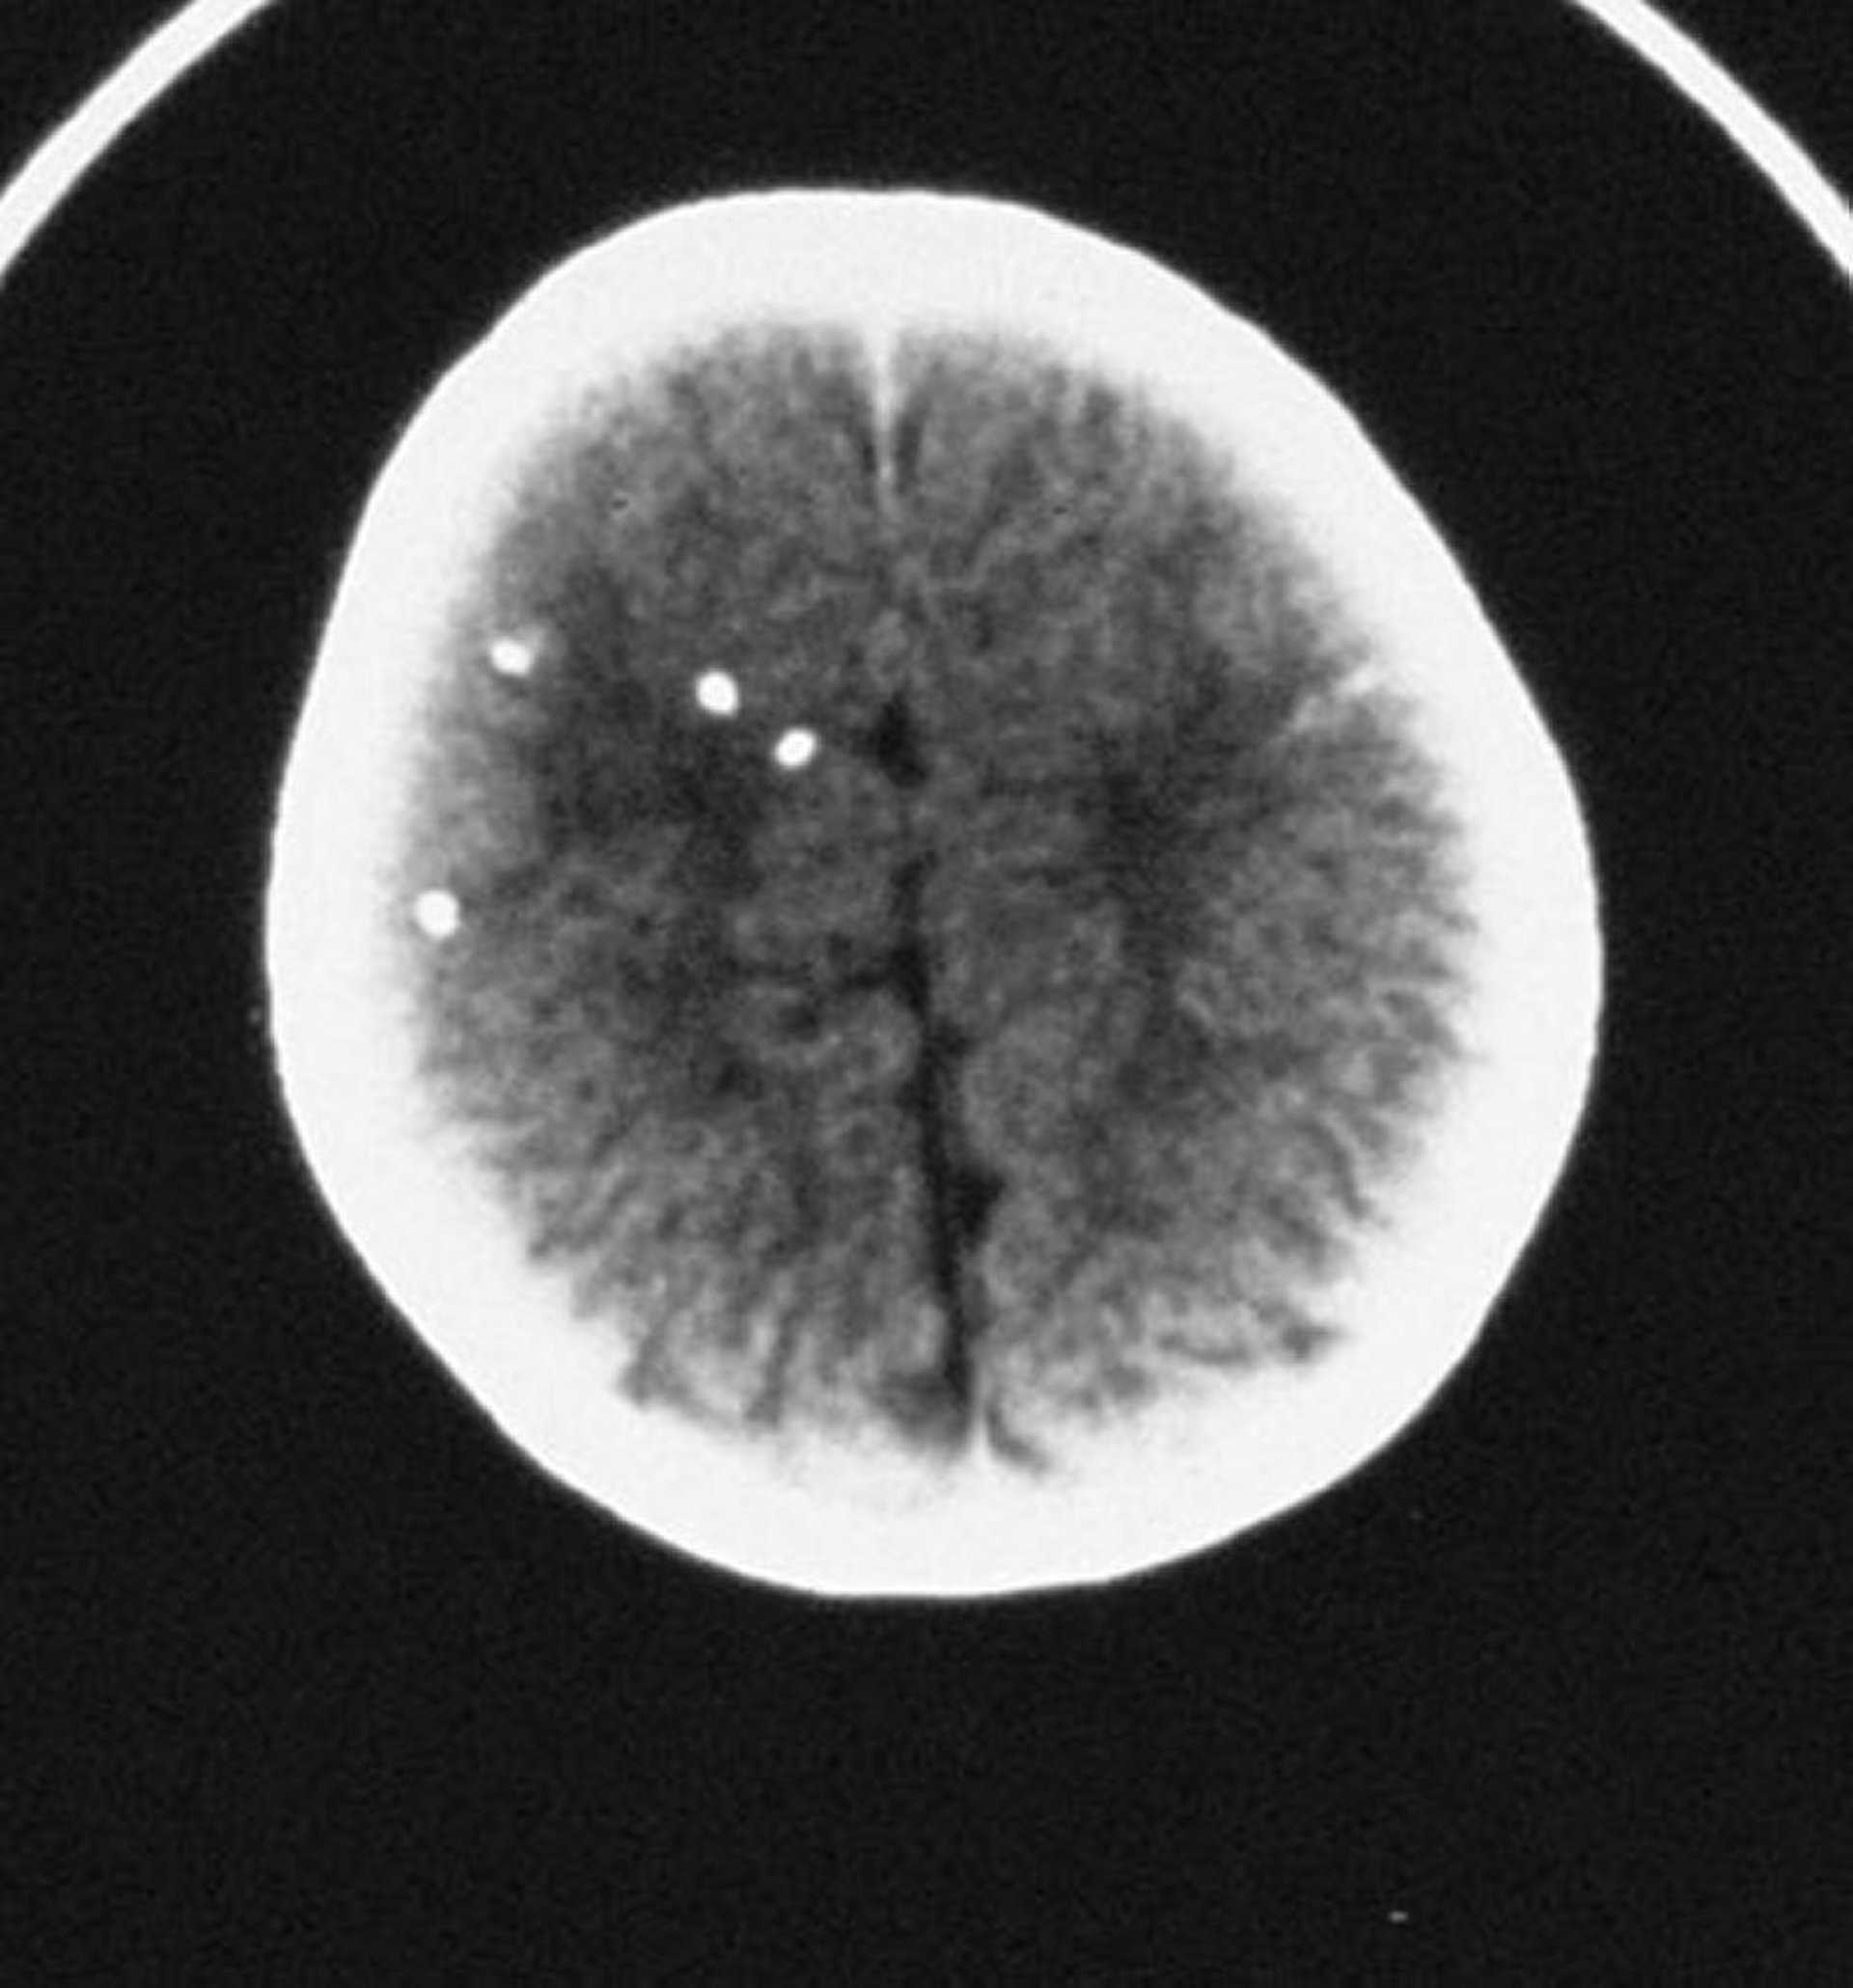

Toxoplasmose congênita

Essa TC mostra calcificações intracranianas esparsas.